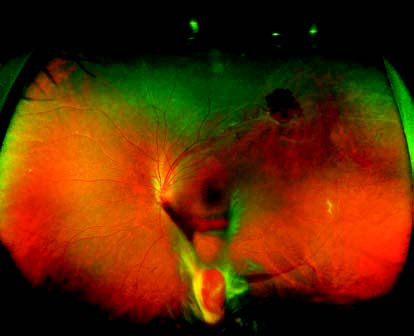

Figure 1 Ultra-widefield fundus photograph of Eales disease in the left eye

The peripheral retina in the superotemporal region of the left eye shows tortuous and dilated venules with perivascular sheathing, accompanied by superficial retinal hemorrhages. The inferior vitreous cavity contains hemorrhagic opacities, with evidence of partial blood organization.

Fundus examination reveals lesions predominantly located in the peripheral retina. Affected retinal venules are dilated and tortuous, surrounded by perivascular sheathing, and accompanied by superficial retinal hemorrhages. Hemorrhages may enter the vitreous cavity, causing varying degrees of vitreous opacity. Recurrent hemorrhages may lead to fibrovascular proliferation or tractional bands, and severe cases may progress to tractional retinal detachment. On fluorescein fundus angiography (FFA), findings include staining of the walls of affected venules, capillary dilation, fluorescein leakage, extensive areas of peripheral capillary non-perfusion, and the formation of neovascular membranes.